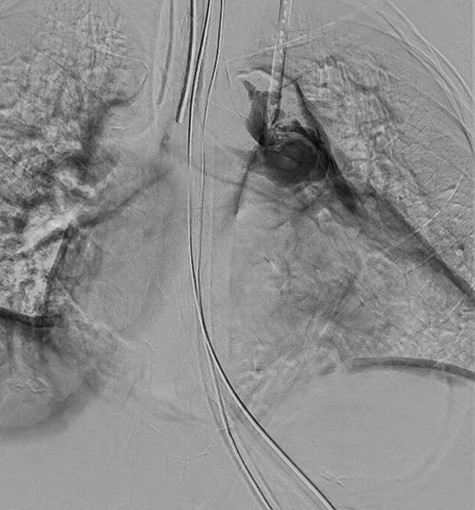

After uncomplicated induction of anesthesia, the patient was anticoagulated with 4000 units of intravenous heparin. The right internal jugular dialysis catheter was removed over a wire placed into the superior vena cava. A large clot was detected in the right subclavian vein, which was treated with angioplasty via the cephalic vein using a 14-mm balloon, resulting in improvement in venous flow. Both access points were closed, and anticoagulation was reversed with 25 mg protamine sulfate 65 minutes after initial heparin bolus. The surgical team then encountered resistance while placing a microwire via the left internal jugular vein into the left subclavian vein for left dialysis catheter placement. After several attempts, the wire was placed under fluoroscopic guidance and the dilator was advanced. During dilator advancement, seen in Fig. 1, resistance was encountered at the cavoatrial junction. Immediately thereafter, the patient experienced profound hypotension and received cardiopulmonary resuscitation (CPR). Intraoperative transesophageal echocardiography imaging demonstrated pericardial tamponade with partial clot. The surgeon obtained large bore vascular access and placed an arterial line in the femoral artery. CPR was stopped after return of spontaneous circulation, with the patient being responsive to vasopressors and further resuscitated with 9 units packed red blood cells, 9 units fresh frozen plasma and 2 units of platelets.

Digital subtraction angiography from operating room fluoroscopy.